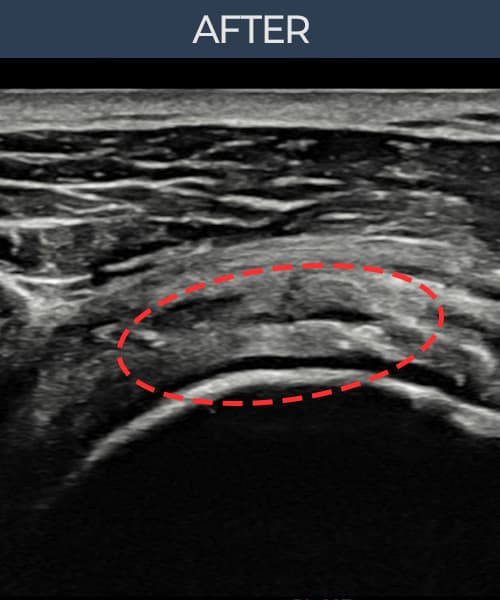

[촬영시기:23.07.31~23.09.27]

[어깨인대 축소봉합술] 좌측 어깨 극상근건 광범위 파열로 수개월간 일상생활이 어렵던 중 내원하셨습니다.